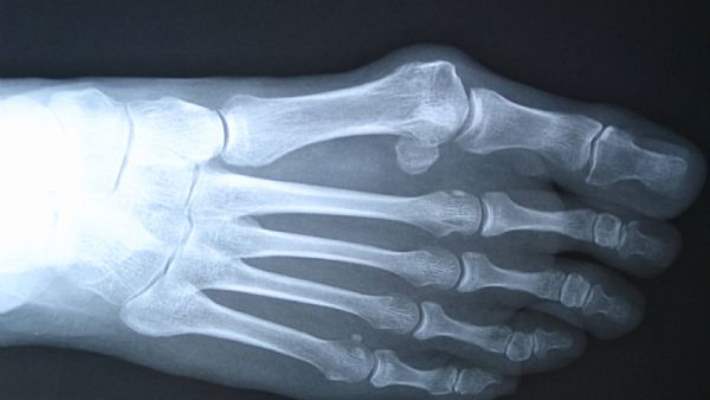

Psödohipoparatiroidizm, normal seviyelerde bulunmasına karşın, paratiroit bezi hormonuna yanıtsızlık ile karakterize, kalıtımsal bir bozukluktur. Bu yetersiz tepki, psödohipoparatiroidizm bulunan kişilerdeki kemik gelişimini etkiler. Bu durumdan etkilenen kişilerde, aynı zamanda baş ağrısı, olağandışı algılar, halsizlik, kolay yorulma, enerji eksikliği, bulanık görme ve / veya ışığa karşı anormal hassasiyet (hipersensitivite) görülür. Ek belirti ve bulgular ise kollarda ve/veya bacaklarda sertlik ve kramplar, çarpıntı ve / veya karın ağrısıdır. Ayrıca, psödohipoparatiroidizm bulunan kişilerde anormal yuvarlak yüz, kalın ve kısa beden, genellikle dördüncü parmaklarda kısalık ve zeka geriliği de görülür. Hormon ve kalsiyum terapisi genellikle işe yarar, ancak gelişim noksanlığı devam edebilir.

Paratroit Hormon Bozukluğu (Psödohipoparatiroidizm)